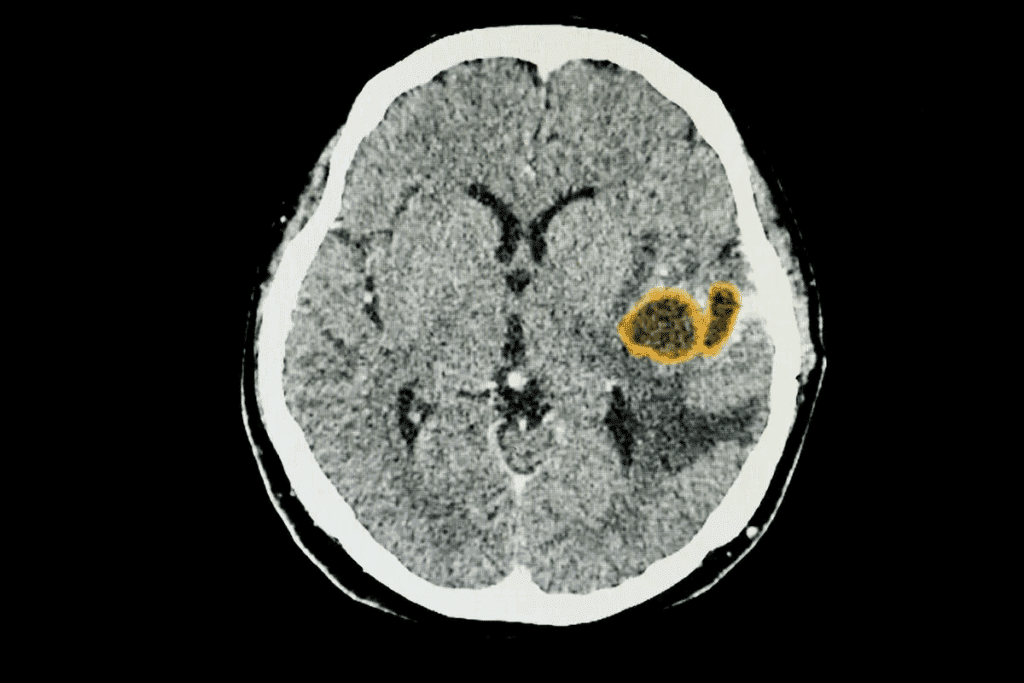

Imaging Studies and DIPG Diagnosis

Imaging studies are vital for DIPG diagnosis. We mainly use MRI (Magnetic Resonance Imaging) to see the tumor. MRI shows the tumor’s size and how it affects the brain.